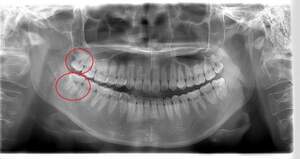

左下親知らずがたまに痛み、

できれば痛くなく抜きたい症例

- 抜歯前写真(レントゲン)

| 親知らずの生え方 | 完全に埋まっている、横向きに生えている |

| 抜歯内容 | 左下親知らずが横向きになって半分埋まっている状態だったため、麻酔を行い、親知らずの奥の歯ぐきに切開をいれ、歯が囲んでいる骨を削り、歯の頭の部分を削って出し、その後根の部分に器具をかけて抜歯しました。 親知らずが一部神経に近い部分があったため、術後に麻痺が出る可能性がありました。このケースでは事前にCTを撮影し、歯の位置、根の方向、神経との距離を確認していたため、幸い麻痺が出ることはありませんでした。 術後1週間経過して糸取りをして治療は終了となりました。抜歯後3日間は腫れと痛みで大変だったが、糸取りをする頃には痛みも腫れも無くなったと患者さまも喜んでおられました。 |